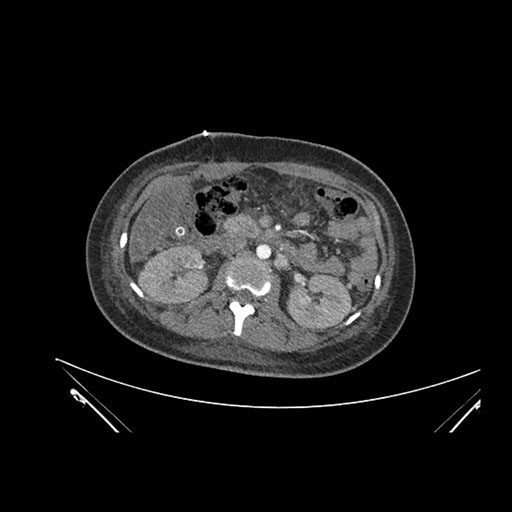

Axial Arterial

Axial Venous

Imaging analysis

Based on initial findings, which issue(s) would you be most concerned about?